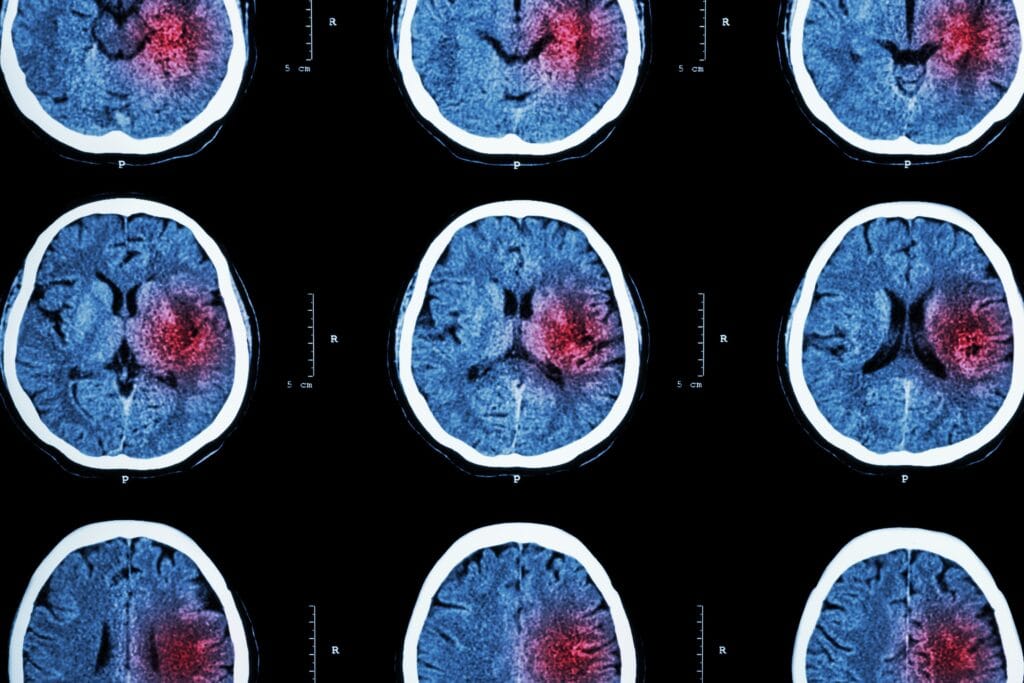

Pecahnya pembuluh darah di otak merupakan kondisi medis serius yang bisa terjadi secara tiba-tiba dan menyebabkan gangguan fungsi otak. Tekanan dari perdarahan dapat merusak jaringan otak dan memicu gejala seperti sakit kepala hebat, kejang, hingga kehilangan kesadaran.

Pecahnya pembuluh darah di otak, atau perdarahan otak, merupakan kondisi serius yang bisa terjadi secara tiba-tiba dan mengancam nyawa. Kondisi ini terjadi ketika pembuluh darah di otak mengalami kerusakan, menyebabkan darah keluar ke jaringan otak di sekitarnya dan menimbulkan tekanan tinggi dalam tengkorak.